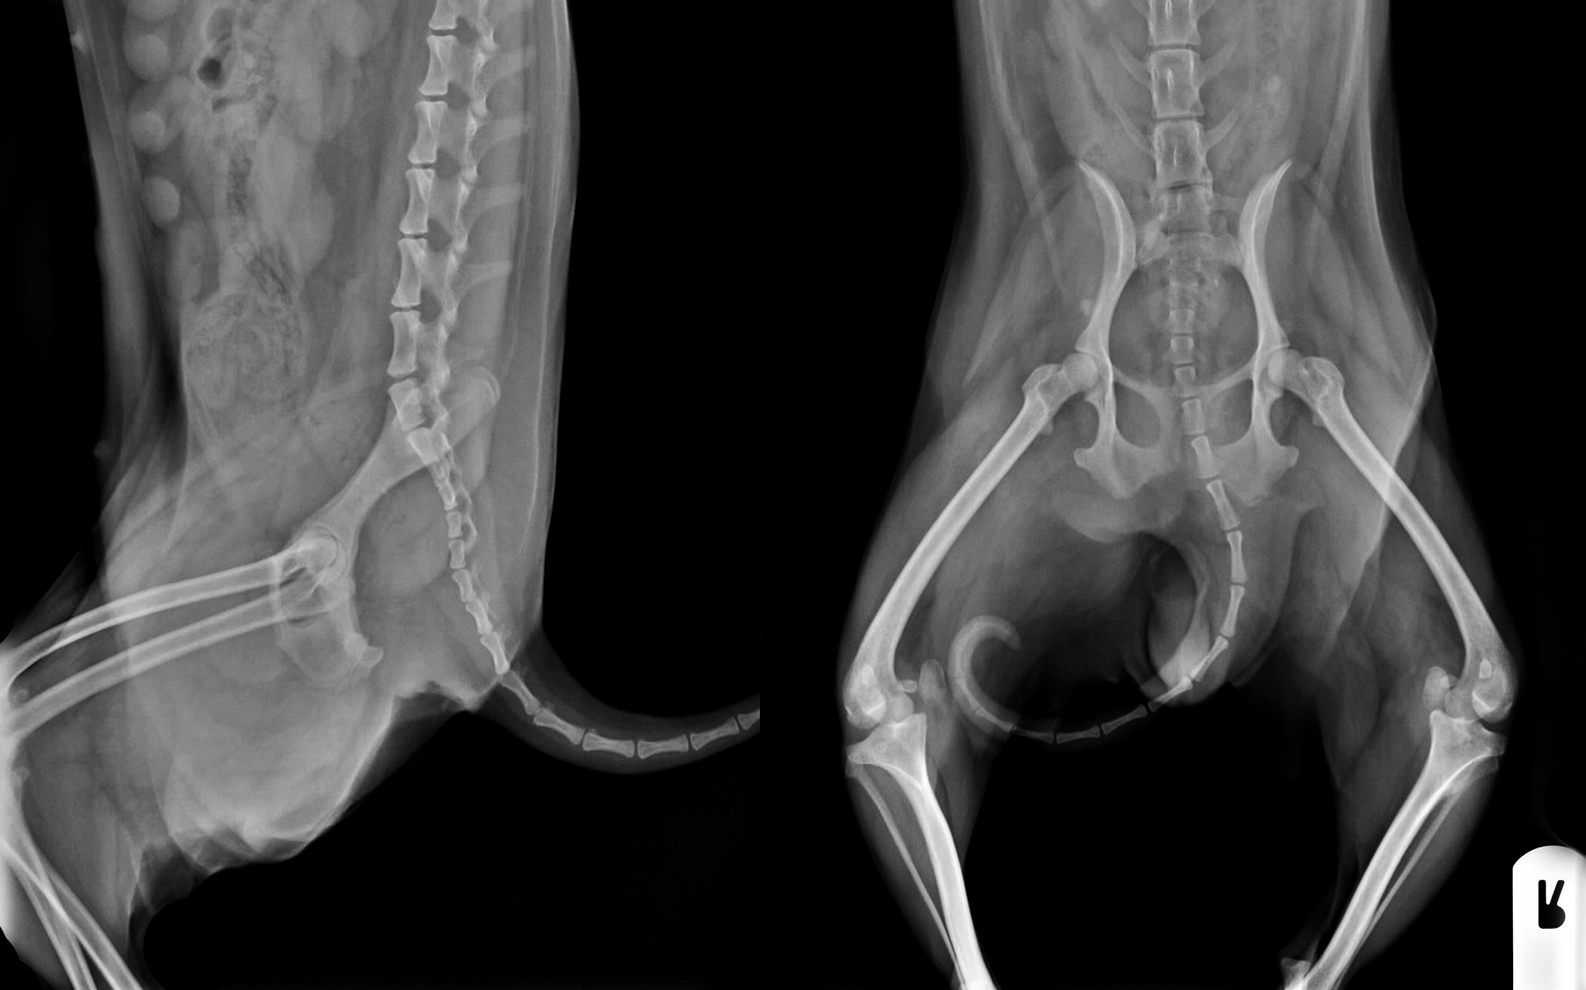

Veamos las primeras imágenes radiográficas:

Es evidente la luxación bilateral de rótulas, pero si nos

fijamos un poco más, la derecha está un poco más cerca del fémur y el grado de

rotación de los huesos es menor.